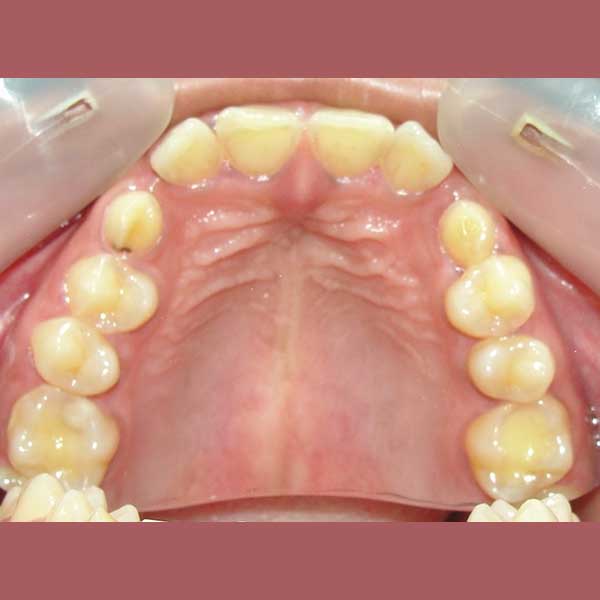

BEFORE

Since she was a child, this woman has suffered from an impacted upper canine -they didn’t erupt in their normal place- and her milky canines were still in her mouth.

By examining the case and taking X-rays, I observed the upper canines in her mouth, and an embedded lower premolar was observed too on the left side, I started the treat the case, but because of the old age of this lady, the upper canines and the left lower premolar did not erupt on their own after we extracted the temporary canines, and she had to pull them out by braces. As for the lower jaw; The canines were pulled back in place and the embedded premolar was orthodontically pulled.